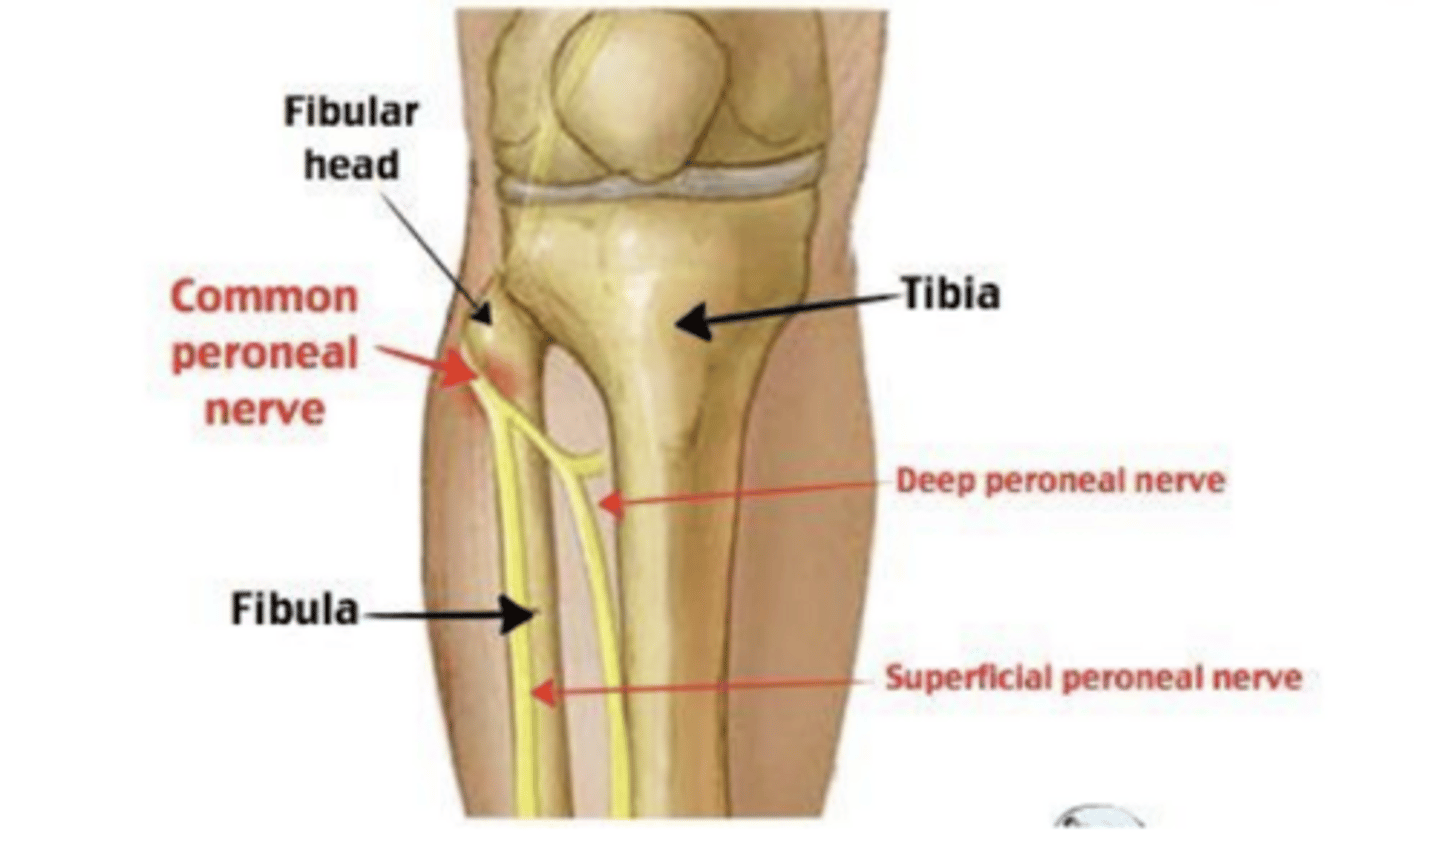

What causes peroneal neuropathy?

Compression, trauma, Crossing legs, Rapid weight loss, Diabetes

What are the physical exam signs of peroneal neuropathy?

Foot drop (weakness in ankle dorsiflexion, toe extension, and ankle eversion), sensory loss over the lateral calf

what is the management of peroneal neuropathy?

spontaneous recovery over weeks-months, weight loss, avoid leg crossing, ankle brace for foot drop, knee pad over lateral knee